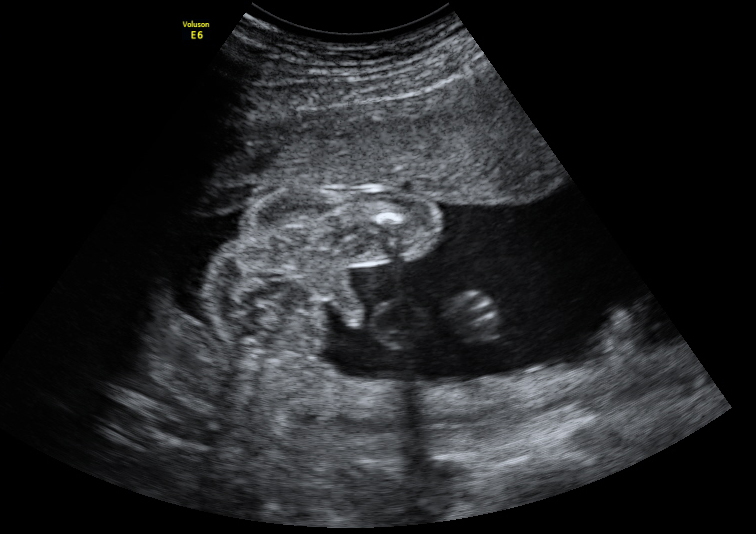

Ecografía de la semana 20: Medición del diámetro biparietal

Ultrasonido de la cabeza fetal

La medición del diámetro biparietal es muy importante en la semana 20 de embarazo. Con esta medida de la cabeza del bebé (sección transversal de la cabeza fetal en el plano adecuado) tal y como vemos en la imagen, el ecografista comprueba el correcto desarrollo de la cabeza fetal.

para la medición del diámetro biparietal (DBP)